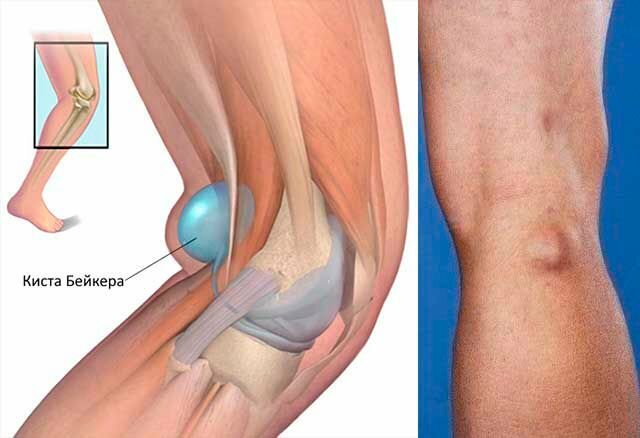

Заболевание сустава: симптомы и лечение